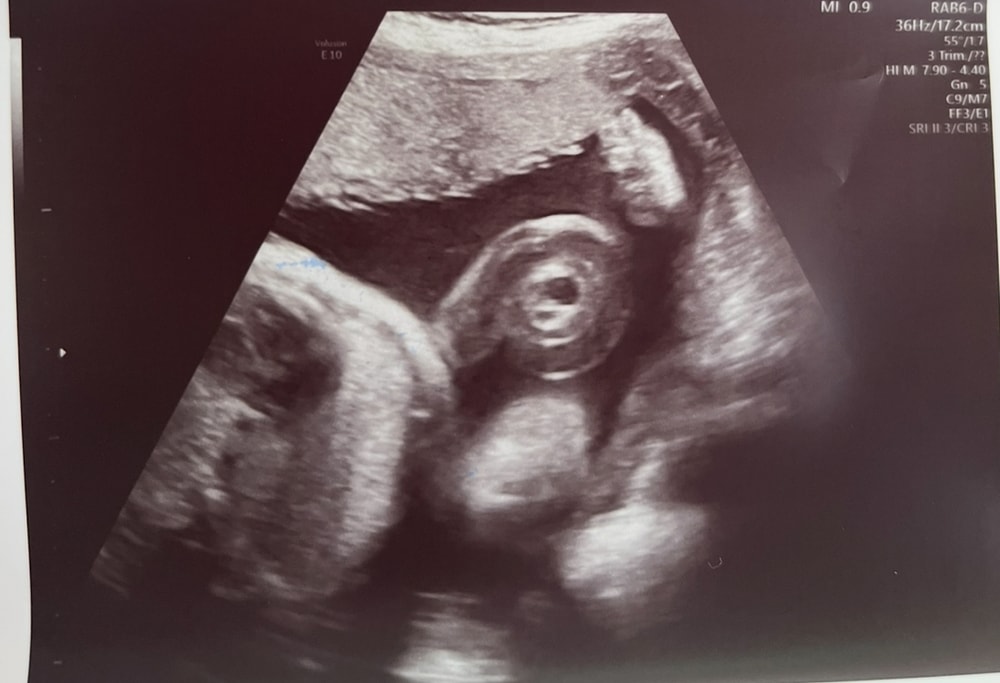

Узел пуповины

Всё о родах (ЕР, КС, вопросы о родоразрешении)У меня срок 30.2, сегодня на 3м скрининге поставили предположение, через неделю пойду за вторым мнением

пс: кровотоки в норме, малышка по развитию опережает на неделю